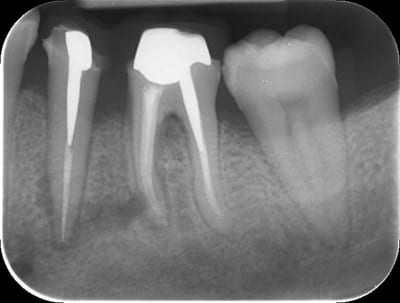

Bonjour, j'ai réalisé la dévitalisation de la 36 avec une anesthésie au quicksleeper avec du 1/100 000 entre la 35 et la 36. Le patient est revenu quelques jours après avec des douleurs et mon conjoint lui a prescrit de l'amoxicilline. J'ai réalisé le traitement de 35 quelques semaines après. Les douleurs s'étaient calmées mais il persistait une sensibilité à la pression et un sondage de 8 mm en distal de 35 et en mésial de 36. Un mois après une suppuration est apparue au niveau de 35 36 mais aussi 34 et 37. J'ai fait une prescription d'augmentin et de flagyl pendant 10 jours.

A ce jour, il n'y a plus de suppuration pas de douleur à la pression sur ces dents mais le vestibule est rouge et légèrement sensible à la palpation. Et la radio n'est pas jolie du tout... Je crains une nécrose osseuse:-(( Dans ce cas, quelle est la conduite à tenir? Merci pour votre aide.

Merci pour ta réponse. J'ai pas enlevé les inlay cores. Les radios sont pas dans l'ordre. La dernière c'est le jour de la préparation pour les IC.